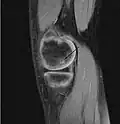

| A large flap lesion in the femur head typical of late stage Osteochondritis dissecans. In this case, the lesion was caused by avascular necrosis of the bone just under the cartilage. | |